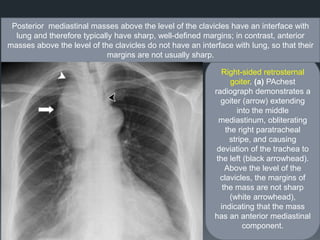

Right-sided retrosternal

goiter. (a) PAchest

radiograph demonstrates a

goiter (arrow) extending

into the middle

mediastinum, obliterating

the right paratracheal

stripe, and causing

deviation of the trachea to

the left (black arrowhead).

Above the level of the

clavicles, the margins of

the mass are not sharp

(white arrowhead),

indicating that the mass

has an anterior mediastinal

component.

Posterior mediastinal masses above the level of the clavicles have an interface with

lung and therefore typically have sharp, well-defined margins; in contrast, anterior

masses above the level of the clavicles do not have an interface with lung, so that their

margins are not usually sharp.